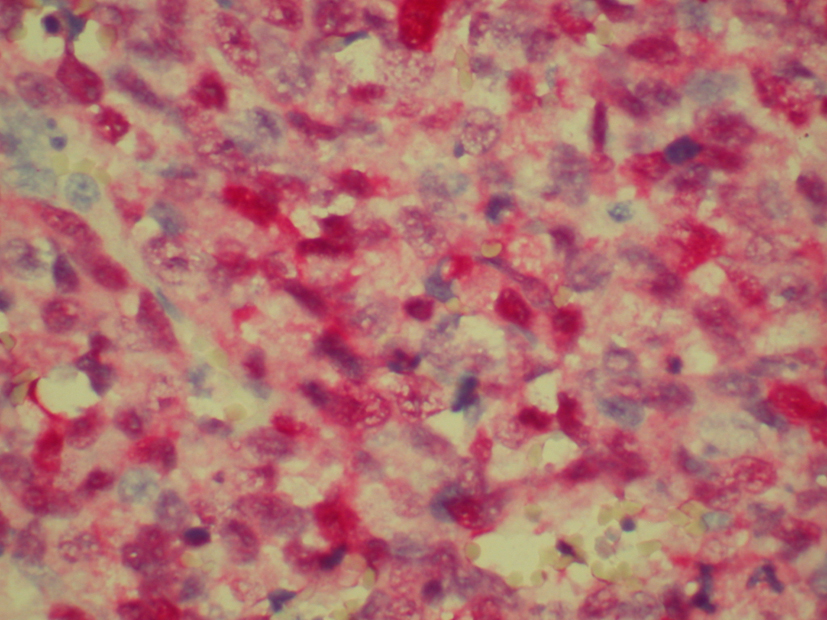

Patient was admitted for prolapsed hemorrhoids. Surgical consult was called and a CT scan of abdomen/pelvis was performed which showed colonic diverticulosis with no acute diverticulitis. The rectal mucosal appeared thickened compared with the remainder of the colon and it was advised that the possibility of a rectal or other colonic neoplasm be excluded (Fig. 1). Biopsy of the rectal mass was performed which showed malignant melanoma. Immunohistochemical stain performed showed the tumor cells to be positive for S-100, melan A and HMB-45 (Fig. 2-4) and negative for CD34, chromogranin, synaptophysin, CD20, AE1/3, CK20, CD3 and CK7. The patient was diagnosed as primary mucosal malignant melanoma. Whole body scan did not reveal any metastasis. Patient was referred to cancer center for further treatment.

![]() Click for large image | Figure 2. Biopsy of rectal mass positive for S-100. |